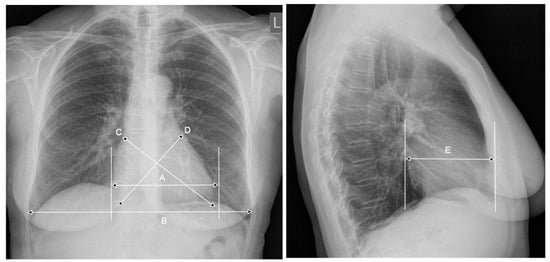

3. CTR—The Meaning of the Breathing Phase, the Anterior-Posterior Heart Dimension